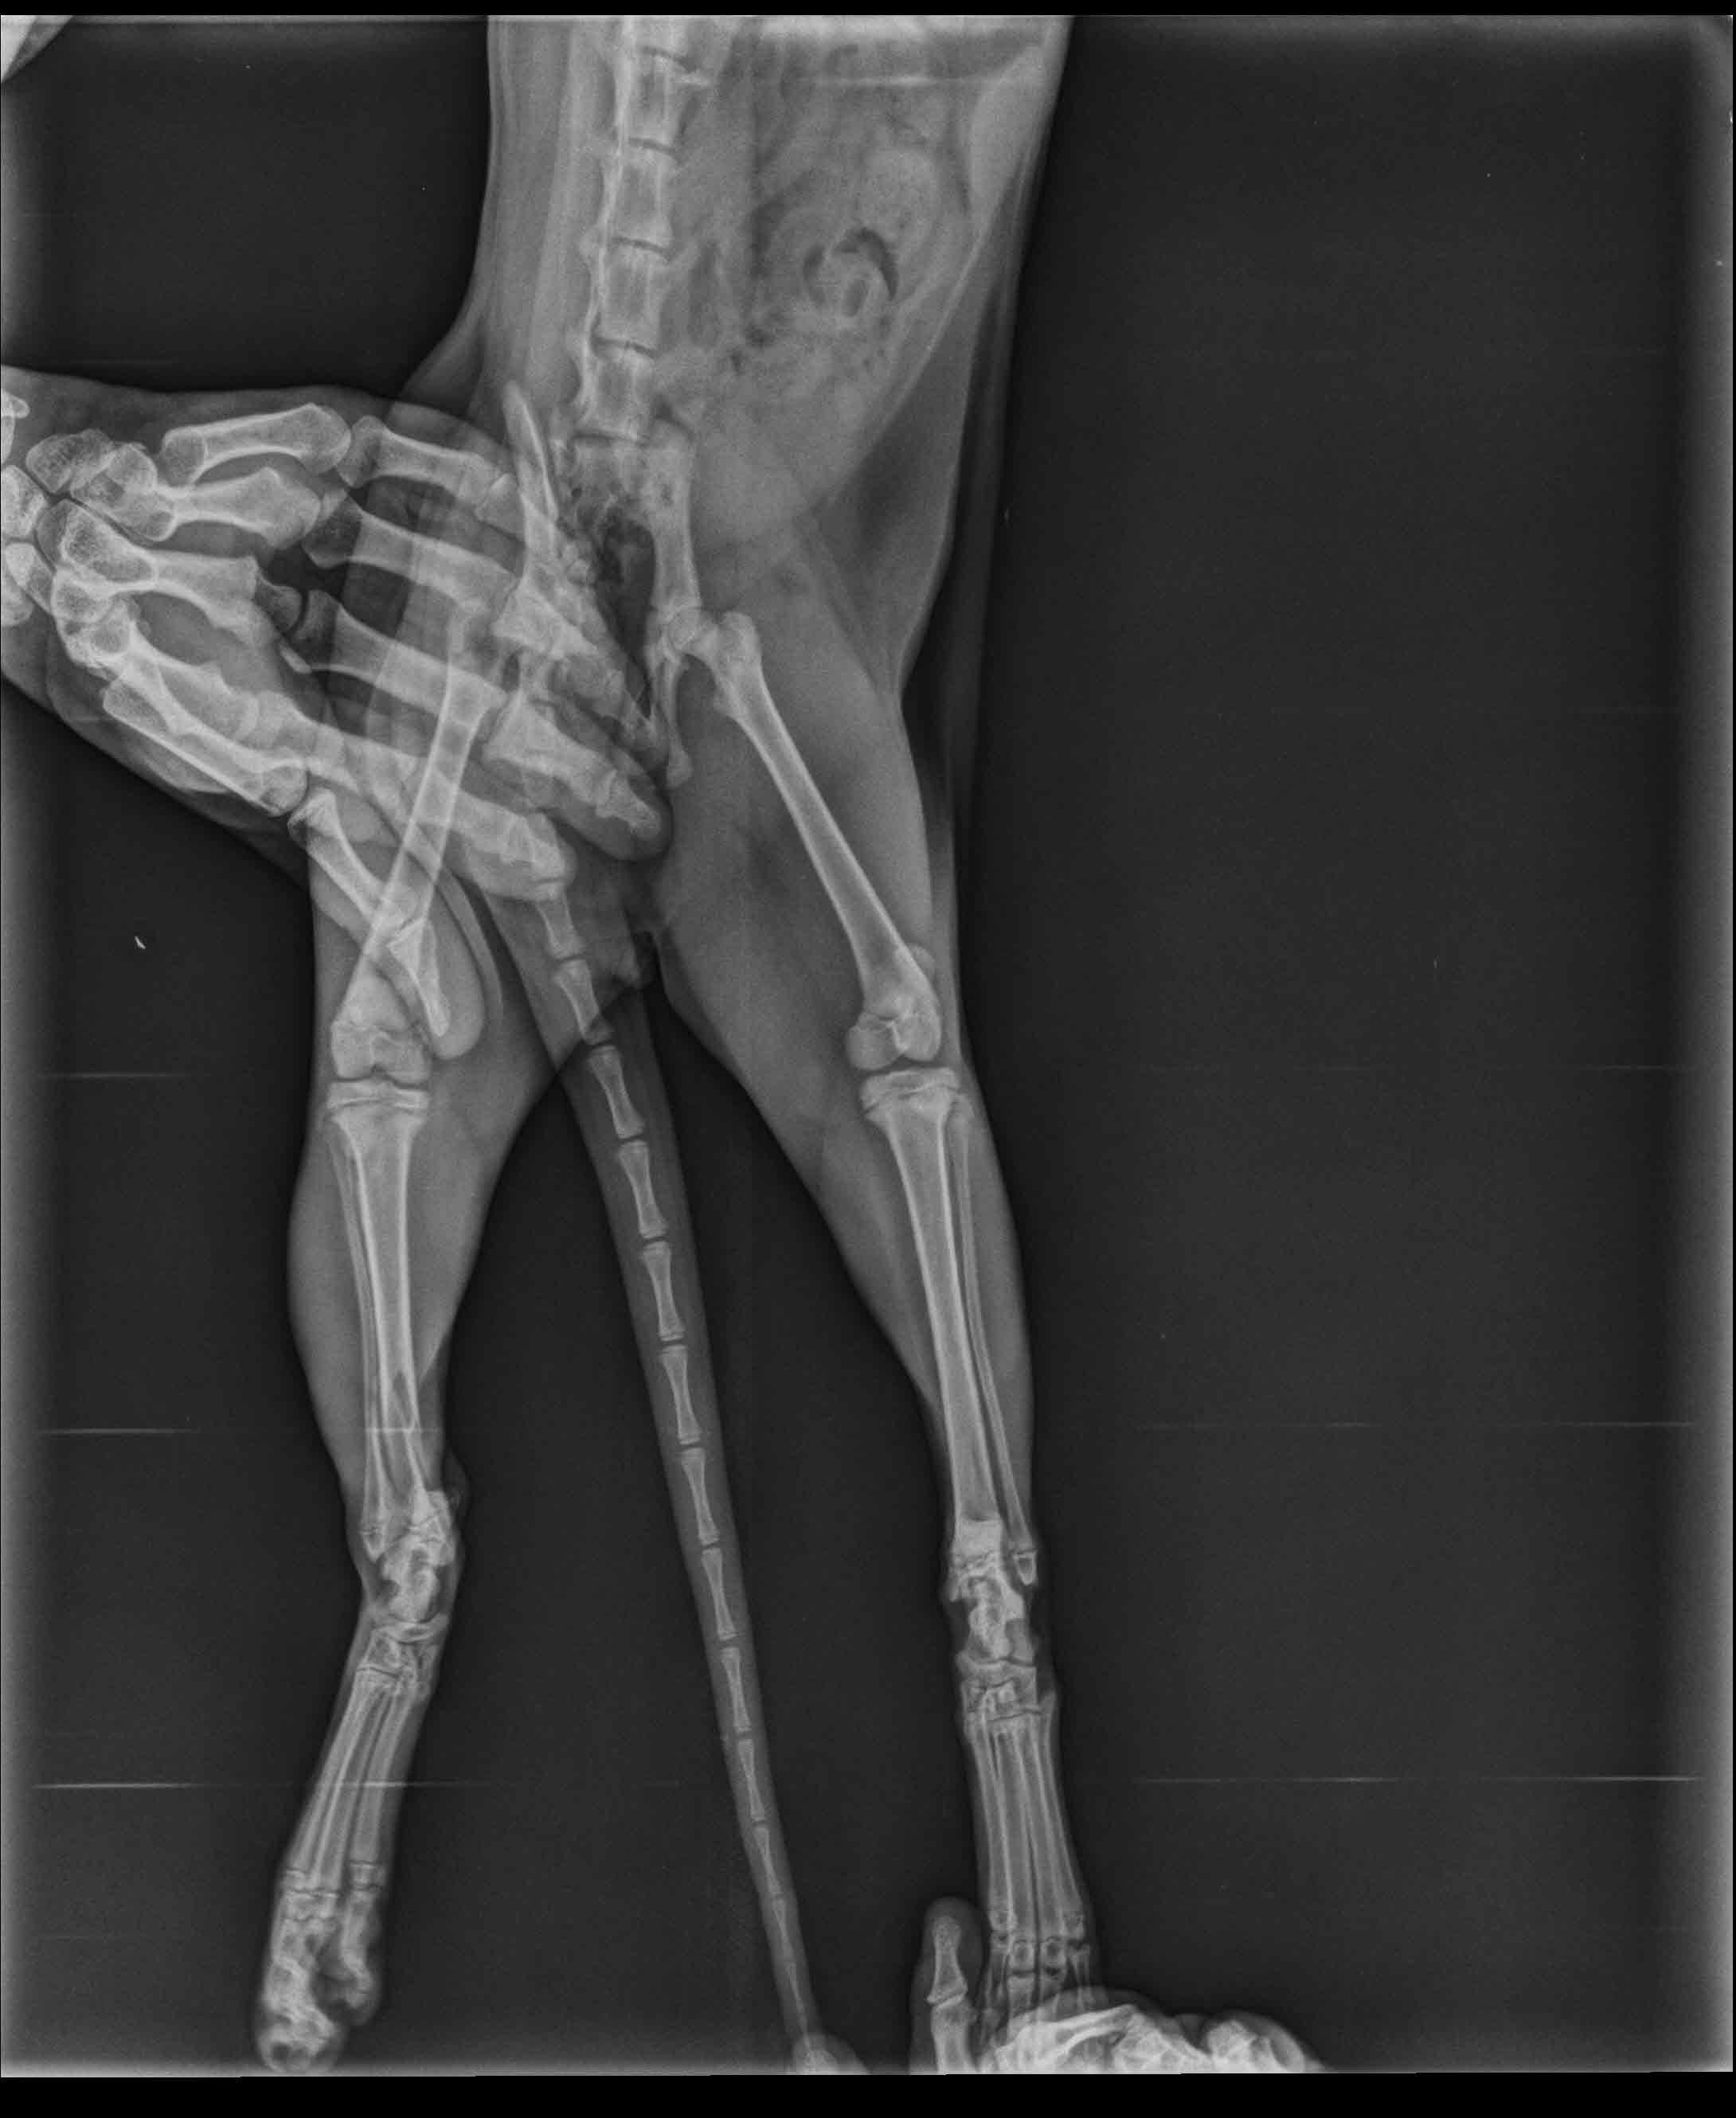

Hello, I have a five months male cat. While he was playing on the table, accidently he fallen down and screamed. After he stand up he start to not stepping on the foot. After veterinary control, they said his foot bone was broken. But i am not sure that it is true. In our country the veterinaries can lied about the situation for earning much money. I atteached the x-ray. Could you check is there a fracture?

I am pretty sure I can see a fracture of the tibia. If you look closely at the third picture and compare the two legs, the long bone right above the foot does not look the same as the other leg. These fractures can usually be healed with splinting or surgery, cage confinement, and pain management.

I am very sorry to hear about your kitty. Unfortunately it does appear he has a broken bone, though in the photo the bone I see broken is actually his leg bone- not the foot. If you look at the bones just above the foot/ankle, the larger of the two long bones has a fracture (this is the tibia). We would need to see an additional view of the bone to know how displaced the fracture is and the best course of action to repair the break.